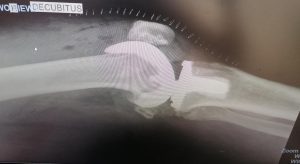

HIGH TIBIAL OSTEOTOMY

Some patients have degeneration of one compartment of the knee, but they are too young to have a total knee replacement. For them it makes sense to change the alignment of the leg so the weightbearing axis runs through the healthy compartment. This allows pain free mobilization for several years. A knee replacement can then be done when the patient is older.

BEFORE OPERATION

AFTER OPERATION